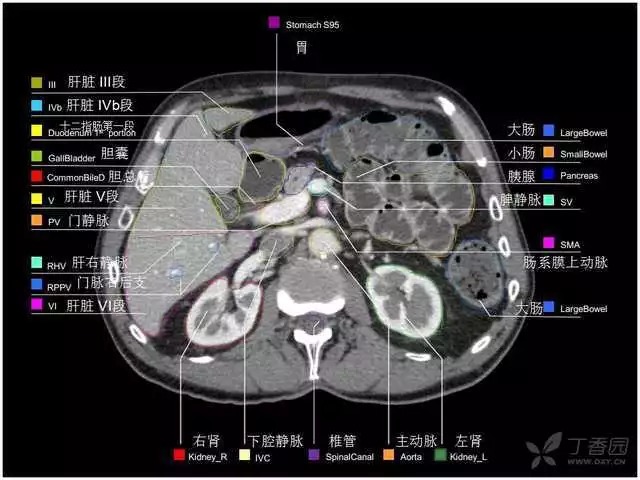

腹部肝脏高清CT断层的图谱

全腹部高清CT图谱,淋巴结彩色图谱,血管解剖图谱大汇总!

肝段,肝内管道的分布规律